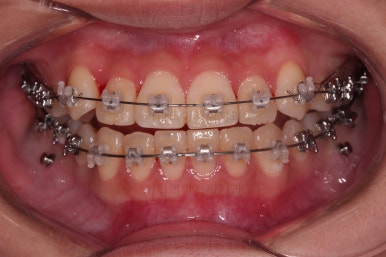

연산동교정치과 교정장치 부착 직후의 모습입니다.

장치가 보이는 느낌이나 입매가 바뀌는 느낌 참고 바랍니다.

이번 환자분은 교정장치를 부착했다해도 거의 입매가 바뀌지 않는 분입니다.

매우 급속도로 가지런해지고 있죠?

대신에 초기 단계에서는 가지런하게 하는데만 초점을 맞추게 되는데 앞니가 뻗치거나 송곳니가 양옆으로 벌어져 보이는 양상을 보입니다.

이제부터는 미니스크류를 이용해서 치열을 뒤로 잡아당겨 주면서 뻗침이나 벌어져 보이는 형태를 개선해 줍니다.

점점 느낌이 좋아지는 걸 볼 수 있죠?